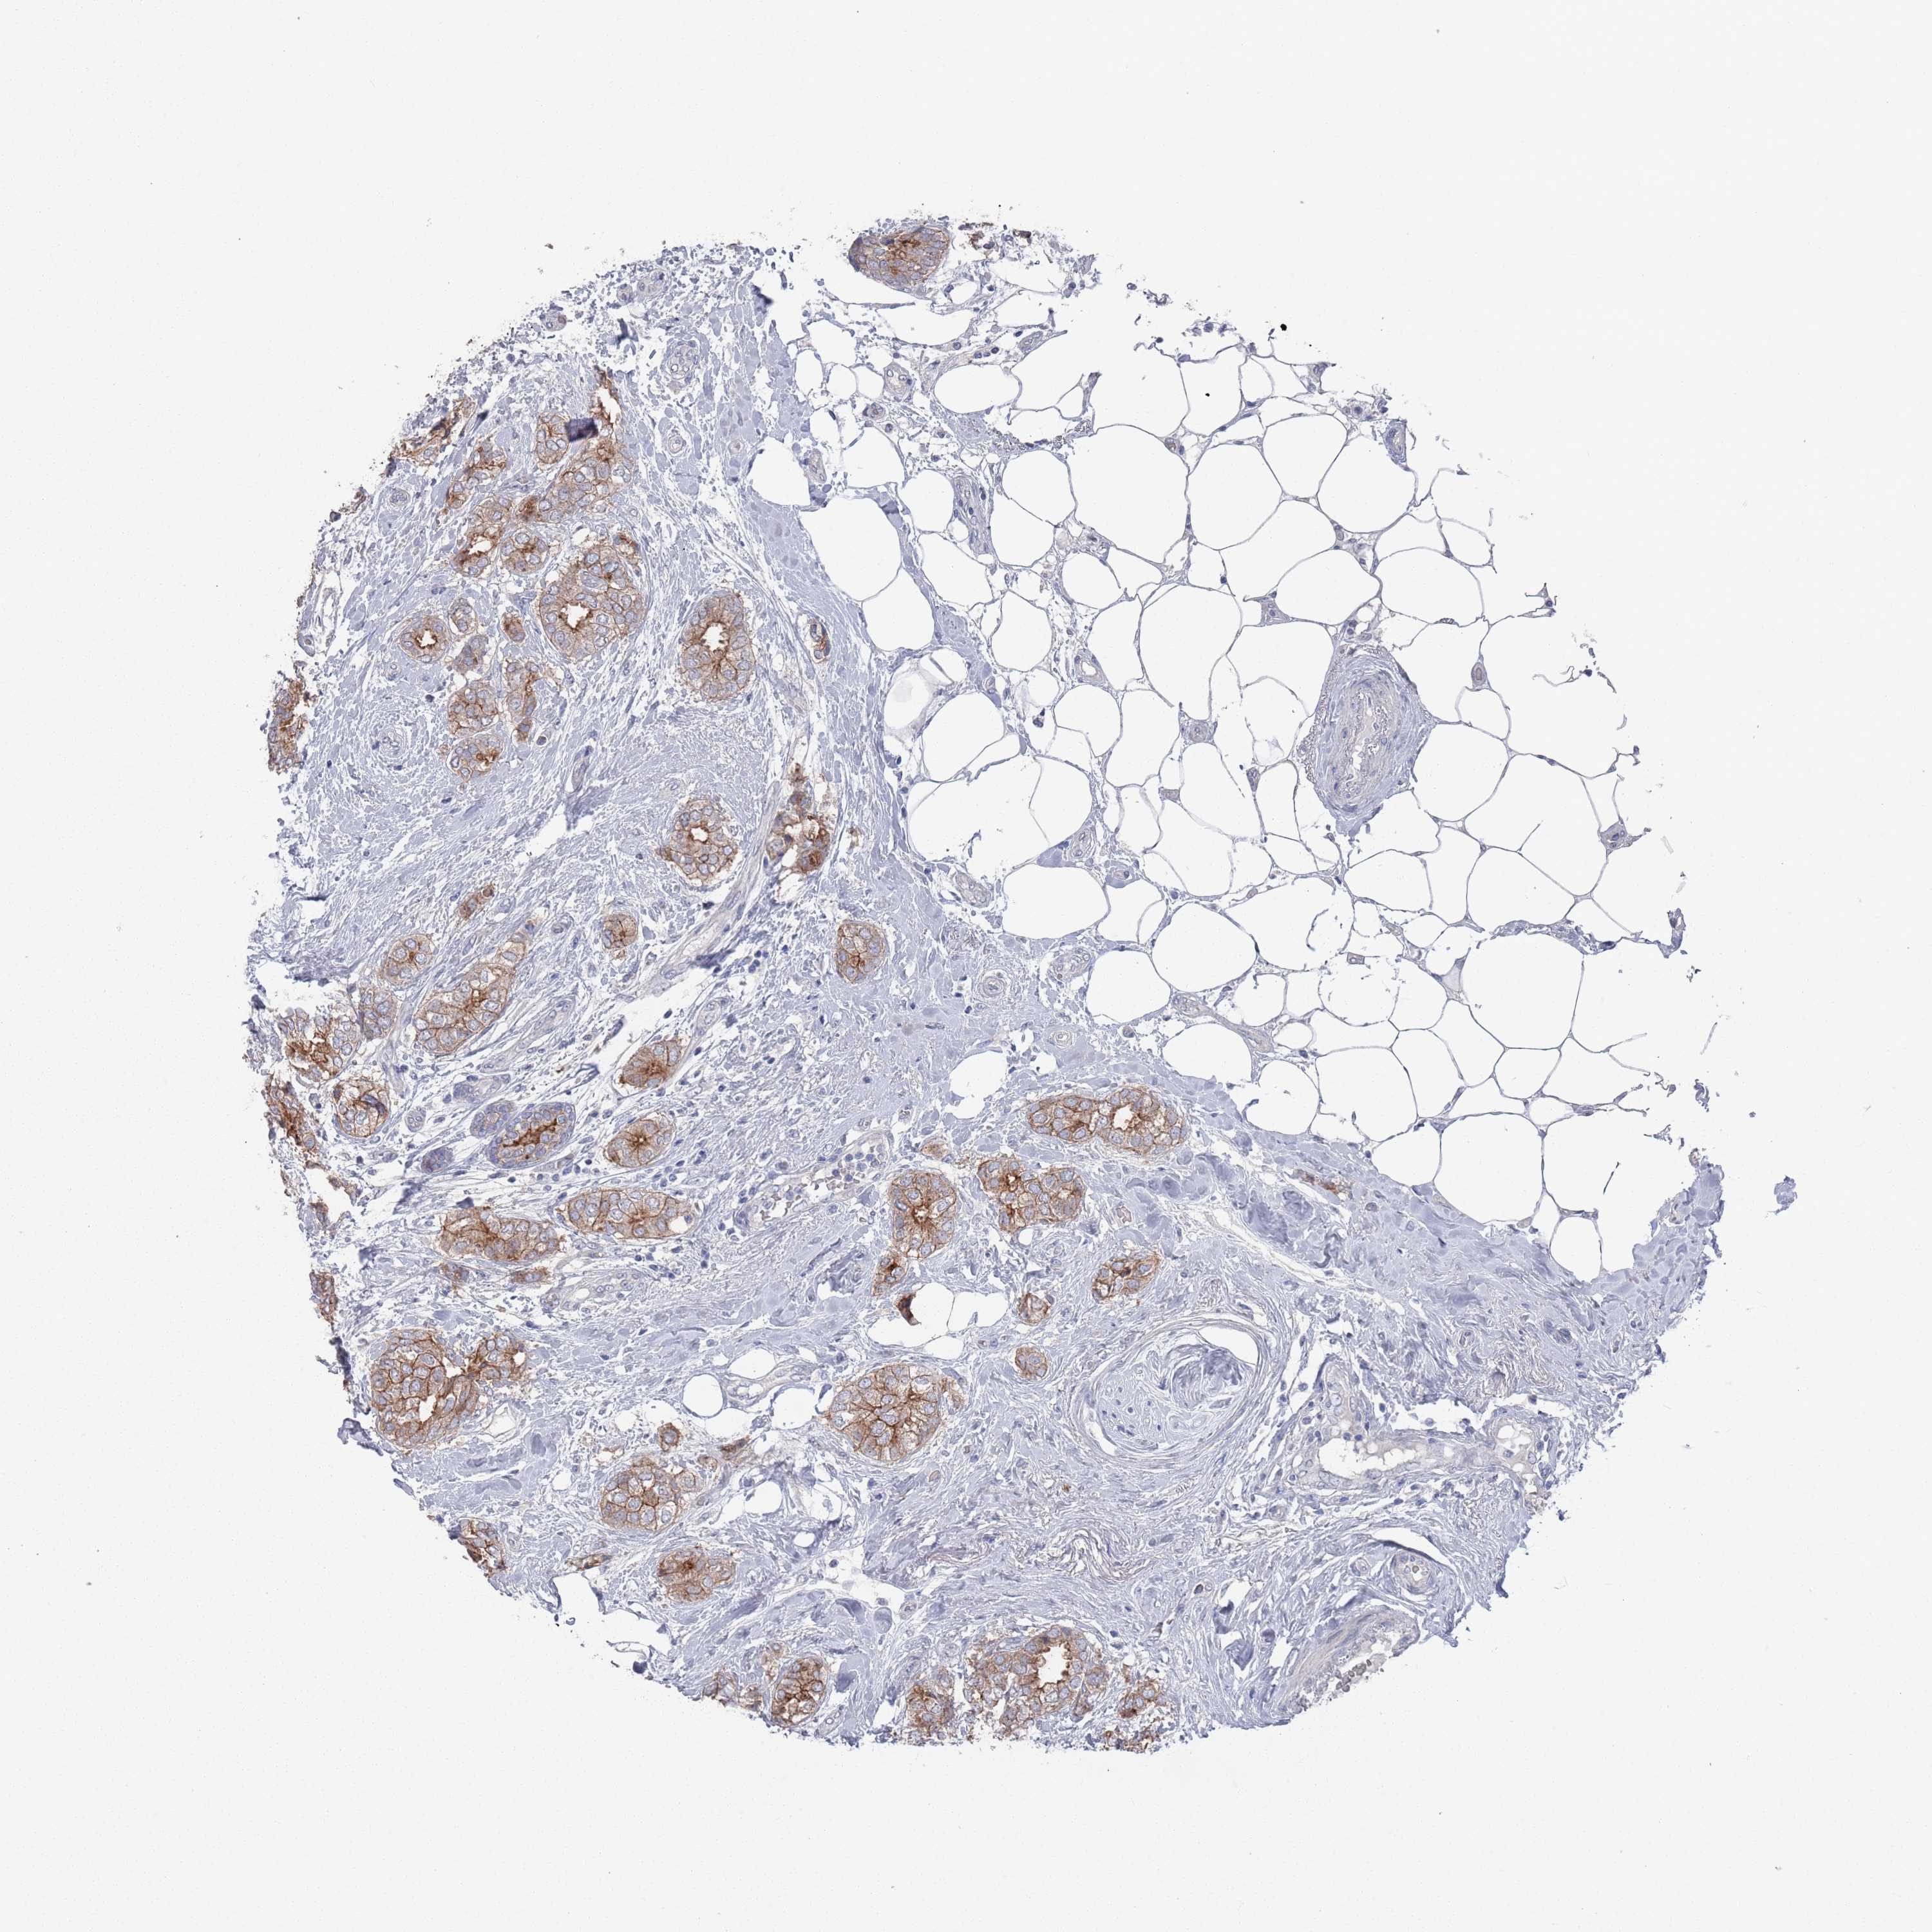

CANCER BREAST CANCER Show tissue menu

BRCA TCGA BRCA VALIDATION PROTEIN EXPRESSION